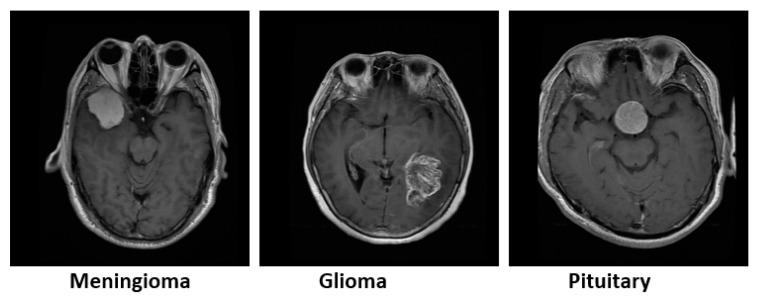

Rapid classification of tumors that are detected in the medical images is of great importance in the early diagnosis of the disease. In this paper, a new liver and brain tumor classification method is proposed by using the power of convolutional neural network (CNN) in feature extraction, the power of discrete wavelet transform (DWT) in signal processing, and the power of long short-term memory (LSTM) in signal classification. A CNN-DWT-LSTM method is proposed to classify the computed tomography (CT) images of livers with tumors and to classify the magnetic resonance (MR) images of brains with tumors. The proposed method classifies liver tumors images as benign or malignant and then classifies brain tumor images as meningioma, glioma, and pituitary. In the hybrid CNN-DWT-LSTM method, the feature vector of the images is obtained from pre-trained AlexNet CNN architecture. The feature vector is reduced but strengthened by applying the single-level one-dimensional discrete wavelet transform (1-D DWT), and it is classified by training with an LSTM network. Under the scope of the study, images of 56 benign and 56 malignant liver tumors that were obtained from Fırat University Research Hospital were used and a publicly available brain tumor dataset were used. The experimental results show that the proposed method had higher performance than classifiers, such as K-nearest neighbors (KNN) and support vector machine (SVM). By using the CNN-DWT-LSTM hybrid method, an accuracy rate of 99.1% was achieved in the liver tumor classification and accuracy rate of 98.6% was achieved in the brain tumor classification. We used two different datasets to demonstrate the performance of the proposed method. Performance measurements show that the proposed method has a satisfactory accuracy rate at the liver tumor and brain tumor classifying.

快速分类在医学图像中检测到的肿瘤在疾病的早期诊断中非常重要。在本文中,通过使用卷积神经网络(CNN)在特征提取、离散小波变换(DWT)在信号处理、长短期记忆(LSTM)在信号分类中的能力,提出了一种新的肝脑肿瘤分类方法。提出了一种 CNN-DWT-LSTM 方法,用于对有肿瘤的 CT 肝脏图像进行分类,对有肿瘤的磁共振(MR)脑图像进行分类。所提出的方法将肝肿瘤图像分类为良性或恶性,然后将脑肿瘤图像分类为脑膜瘤、神经胶质瘤和垂体瘤。在混合 CNN-DWT-LSTM 方法中,从预先训练的 AlexNet CNN 架构获得图像的特征向量。通过应用单级一维离散小波变换(1-D DWT)对特征向量进行降维和增强,然后通过 LSTM 网络进行训练进行分类。在研究范围内,使用了来自 Firat 大学研究医院的 56 个良性和 56 个恶性肝肿瘤的图像和一个公开可用的脑肿瘤数据集。实验结果表明,与 K 最近邻(KNN)和支持向量机(SVM)等分类器相比,所提出的方法具有更高的性能。通过使用 CNN-DWT-LSTM 混合方法,在肝肿瘤分类中达到了 99.1%的准确率,在脑肿瘤分类中达到了 98.6%的准确率。我们使用了两个不同的数据集来证明所提出方法的性能。性能测量表明,所提出的方法在肝肿瘤和脑肿瘤分类中具有令人满意的准确率。